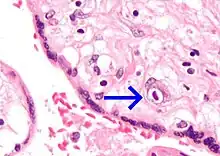

- Placentitis, inflammation of the placenta, such as by TORCH infections.

Micrograph of CMV placentitis

Micrograph of CMV placentitis A 3D Power Doppler image of vasculature in 20-week placenta